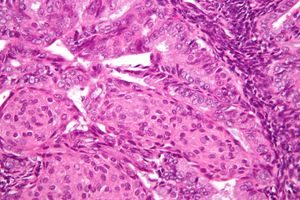

자궁내막암의 조직병리학적 소견은 매우 다양하다. 가장 흔한 소견은 분화가 잘된 자궁내막양 선암종[44]이며, 이는 핵의 비정형성, 분열 활성 및 층화 정도가 다양한 수많은 작고 밀집된 선으로 구성된다. 이는 종종 자궁내막 증식증을 배경으로 나타난다. 명백한 선암종은 명확한 기질 침윤, 즉 암에 의해 자궁내막 기질이 비파괴적으로 대체되어 나타나는 "맞닿아 있는" 선의 소견으로 비정형 증식증과 구별될 수 있다. 질병이 진행됨에 따라 근육층이 침윤된다.[54]